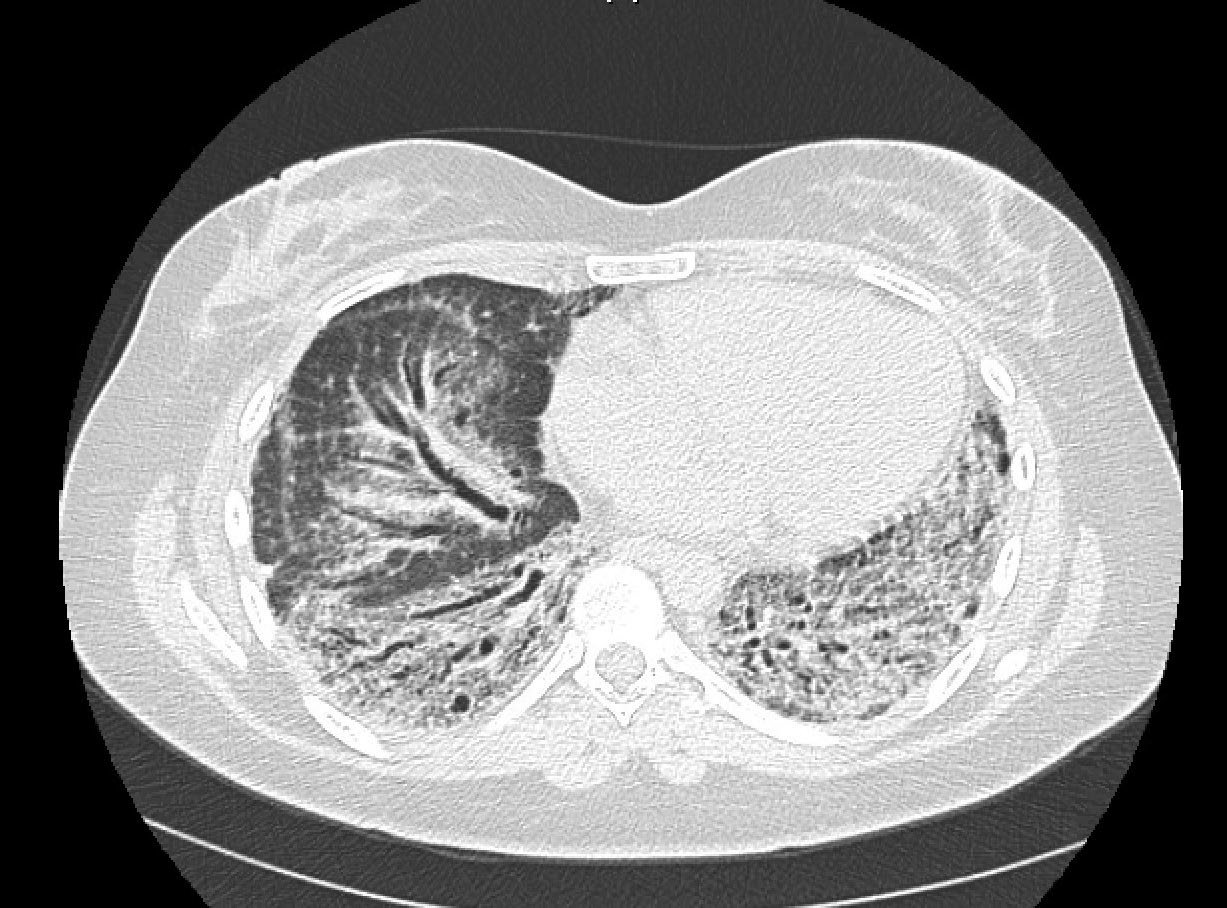

A 39-year-old woman with former tobacco use (4.5 pack-years) presented with rapidly progressive interstitial lung disease (ILD). Two years prior, the patient developed subacute exertional dyspnea and cough, for which she received antibiotics without improvement. One year later, she developed diffuse arthralgias (hands, wrists, knees, ankles), xerophthalmia, xerostomia, and worsening dyspnea. Computed tomography (CT) scan of the chest revealed extensive peripheral honeycombing, traction bronchiectasis, and lower lobe predominant ground-glass opacities (Fig. 1). Laboratory testing was notable for positive antinuclear antibody (1:320, speckled) and Sjogren’s syndrome A (anti-SSA) autoantibody. Other laboratory results were unremarkable including rheumatoid factor and serum antibodies to Sjogren’s syndrome B (anti-SSB), anti-Smith, anti-RNP, anti-double-stranded DNA, anti-topoisomerase, anticentromere, RNA polymerase III, myeloperoxidase, serine proteinase 3, anti-Jo-1 (and extended myositis panel), and cyclic citrullinated peptide. Evaluation for infectious etiologies (HIV, tuberculosis, and pulmonary bacterial, viral, and fungal pathogens) was unremarkable.

Figure 1: Chest CT scan without contrast demonstrates extensive peripheral areas of honeycombing, areas of traction bronchiectasis, and scattered ground-glass opacities with a lower lobe predominance.